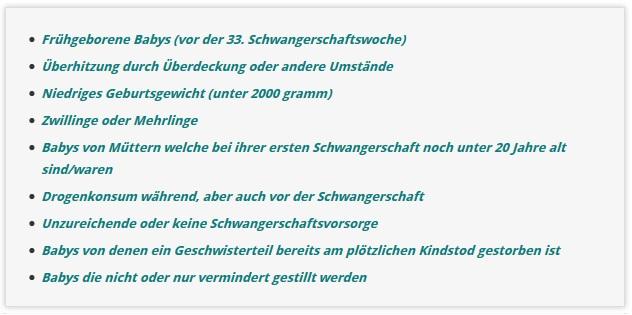

Risikofaktoren für den plötzlichen Kindstod:

Einige mögliche Risikofaktoren für den plötzlichen Kindstod sind: